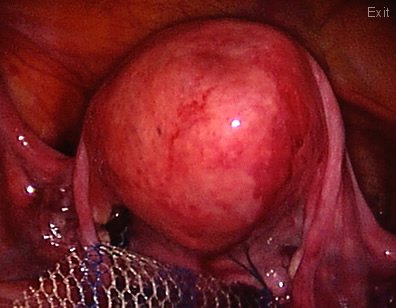

This other patient has a very troublesome prolapse: A vaginal eversion. The vaginal canal is coming "inside out".

In this patient with a vaginal eversion; a mesh is attached to the vaginal vault and the vagina is pulled towards the pelvic cavity. The other end of the mesh will be attached to the sacrum bone (sacrum promontorium) to restore the normal anatomy.